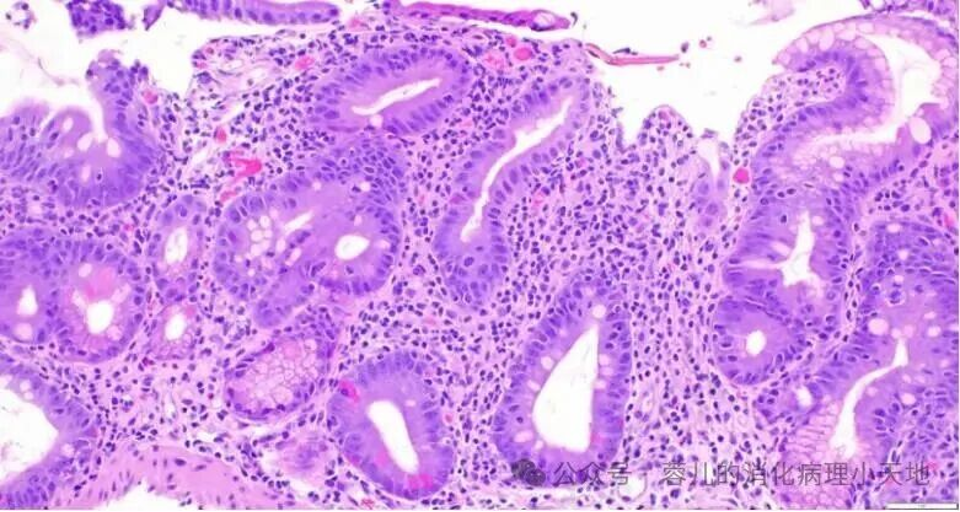

接受 CAR-T 疗法的患者十二指肠:黏膜深层可见斑片状异质性绒毛变钝,伴小凹/胃上皮化生、凋亡性脓肿、隐窝凋亡小体增多以及显著的上皮内淋巴细胞;固有层细胞增多;但无浆细胞。

接受 CAR-T 疗法的患者十二指肠。黏膜深层可见斑片状异质性绒毛变钝,伴小凹/胃上皮化生、凋亡性脓肿、隐窝凋亡小体增多以及显著的上皮内淋巴细胞;固有层细胞增多;但无浆细胞。